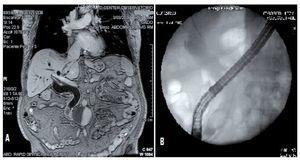

A 69 years old hispanic male with a 4 month history of painless jaundice who was diagnosed elsewhere with unresectable cholangiocarcinoma came to our institution looking for a second opinion and further treatment. Physical exam, except for jaundice was unremarkable. Liver function tests reported total bilirubin 6 mg/dL, direct bilirubin 4 mg/dL, alkaline phosphatase 290 U/L, gammaglutamyl transpeptidase (GGT) 180 U/L, aspartate aminotransferase (AST) 175 U/L and alanine aminotransferase (ALT) 160 U/L. Magnetic resonance cholangiography (MRCP) showed significant intra and extrahepatic bile duct dilatation and a hypointense area within the distal common bile duct (CBD) (Figure 1-A) suggesting a stone. An endoscopic retrograde cholangiopancreatography (ERCP) showed a large stone impacted within the distal CBD (Figure 1-B). The stone could not be retrieved using standard extraction procedures (biliary sphincterotomy, retrieval balloon and/or use of Dormia basket) due to size. Even though mechanical lithotripsy is the modality used most commonly, it was omitted to simplify the process of stone extraction and to reduce costs. In order to choose the right size of the balloon to be used, the bile duct and stone diameters were measured during ERCP with the external diameter (13.2 mm) of the distal end of the duodenoscope (Olympus Evis Exera TJF-160VF). The biliar sphincterotomy was extended and the balloon catheter (CRETM wireguided balloon dilator 15 - 18 mm, Boston Scientific) was passed over a guidewire and positioned at the biliary orifice. Then, the balloon was gradually filled up to 15 mm with water and diluted contrast medium by using an inflation device (ALLIANCE II, Boston Scientific). The fully expanded balloon was maintained in position for 45 seconds after it was collapsed and removed. A Dormia basket was then used to remove the stone. A 25 mm x 30 mm CBD stone was extracted uneventfully except for minor oozing that stopped spontaneously (Figure 2). After the procedure the patient was hospitalized for observation with no clinical evidence of bleeding or pancreatitis; hemoglobin and serum amylase levels were measured 18 hours after the procedure within normal limits. The patient was discharged without complications. One month after the endoscopic intervention no complications were observed.

¿ Figure 1. A MRCP image; B ERCP fluoroscopic image showing a large stone impacted on distal CBD.